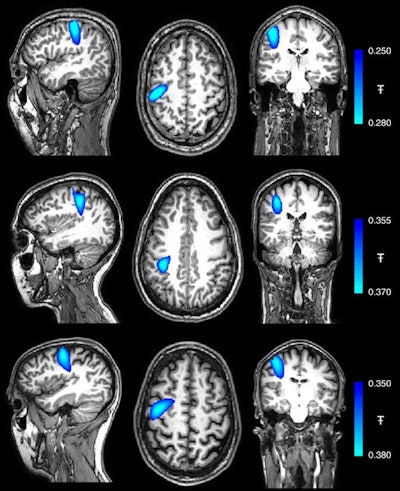

The researchers used these images, as well as data from a motion-tracking camera, to coregister the location and orientation of the helmet OPMs relative to the participants' head. This technique ultimately allowed them to generate 3D images representing changes to beta brainwave activity.

Coregistereed images showing the spatial signature of beta modulation; the largest peak was found in precentral-sulcus (motor cortex) in all three subjects. Image courtesy of Hill et al. Licensed under CC BY-NC 4.0.Following the early tests, Hill and colleagues used their MEG scanner to examine the brain activity of a 14-year-old teenager while completing a simple, repetitive task on a computer and of a 24-year-old woman as she played a ukulele.

Despite the substantial head movement that these tasks required, the MEG scanner was able to record clear electrophysiological responses in the brain. Of note, the largest change in brain activity while the participants performed their respective tasks occurred in the contralateral primary somatosensory cortex of the brain.